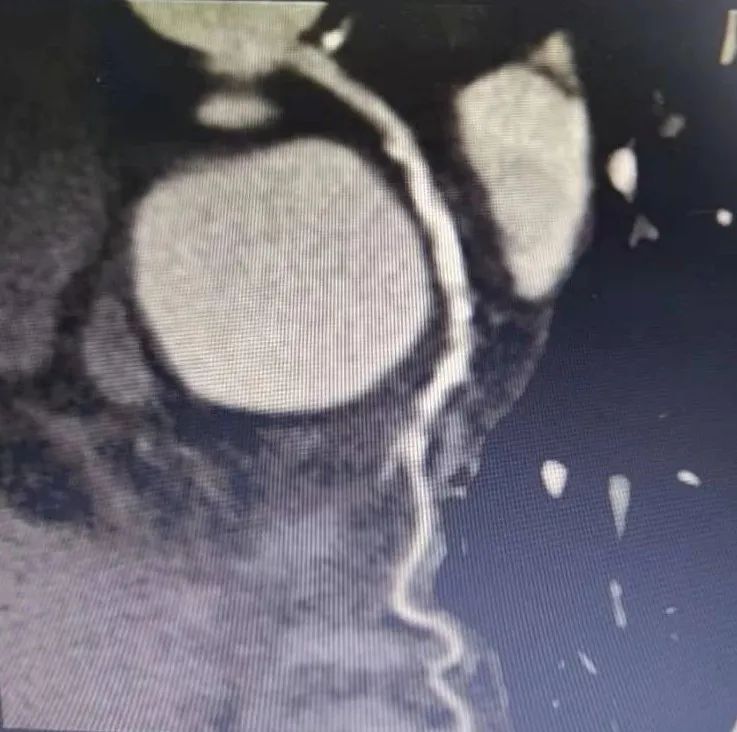

冠脉CTA显示LCX狭窄伴钙化

患者为78岁女性,主因间断胸闷3年就诊,冠状动脉CTA提示冠状动脉严重钙化,左主干管壁多发钙化,管腔狭窄,前降支严重钙化伴管腔狭窄大于70%,回旋支严重钙化伴有管腔严重狭窄。由于钙化严重,术前刘巍主任团队就做好了充分的准备。冠状动脉造影提示左前降支严重钙化伴有多发斑块管腔偏细,回旋支远段85%狭窄,右冠状动脉全程钙化伴有多发斑块。计划使用IVUS对回旋支狭窄进行评估,但IVUS无法通过近段病变,IVUS提示近段钙化角度大于270°。刘巍主任使用1.25mm磨头对回旋支进行旋磨,旋磨后,球囊及IVUS可顺利通过钙化病变到达远端,IVUS提示管腔弥漫性斑块,斑块负荷重,远段管腔严重狭窄,刘巍主任决定植入支架,经旋磨后,支架可顺利通过钙化病变部位,成功释放,支架膨胀效果良好。术后患者胸闷明显缓解。